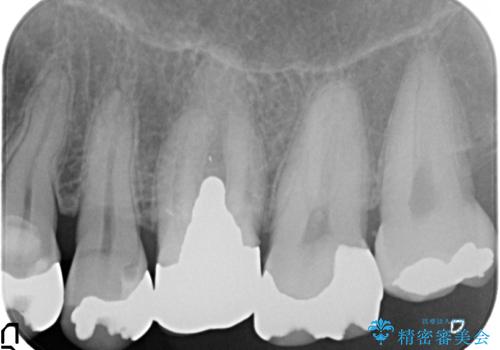

- 失ってしまった左下の奥歯にインプラント治療を受けたいと来院されました。

左下の欠損部には強度・表面性状に優れるストローマン社製インプラントを埋入し、合わせて噛み合う上顎の歯もクラウン再補綴による整備を行い安定した咬合関係の構築を目指します。

歯を失った期間が長くなると、対合する歯が伸びてくることによる補綴スペースの狭小化がしばしば見られます。

今回左下にインプラント治療を行うにあたり、対合する上顎の歯もいっしょに治療を行ったことで安定した咬合関係を構築することができました。